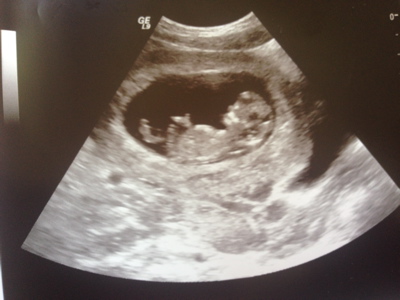

Hello! I'm new to this forum but I'd love to hear what you guess from our 12 week 0 day ultrasound. I really appreciate you taking the time to guess. Skull and Nub guesses would be great! Thanks so much!

Attachment 18911